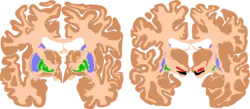

The basal ganglia plays essential roles in voluntary motor function. Various forms of damage to the basal ganglia can cause a range of movement disorders.

Like other forms of CP, it is primarily associated with damage to the basal ganglia in the form of lesions that occur during brain development due to bilirubin encephalopathy and hypoxic–ischemic brain injury.[7]

Multiple classification systems using magnetic resonance imaging (MRI) have been developed, linking brain lesions to time of birth, cerebral palsy subtype and functional ability.[23][24][25][26] Around 70% of patients with DCP show lesions in the cortical and deep grey matter of the brain, more specifically in the basal ganglia and thalamus. However, other brain lesions and even normal-appearing MRI findings can occur, for example white matter lesions and brain maldevelopments.[2][25][27][28] Patients with pure basal ganglia and thalamus lesions are more likely to show more severe choreoathetosis whereas dystonia may be associated with other brain lesions, such as the cerebellum.[2] These lesions occur mostly during the peri- and postnatal period since these regions have a high vulnerability during the late third trimester of the pregnancy.[29] Unfortunately, contemporary imaging is not sophisticated enough to detect all subtle brain deformities and network disorders in dystonia. Research with more refined imaging techniques including diffusion tensor imaging and functional MRI is required.[10][30]